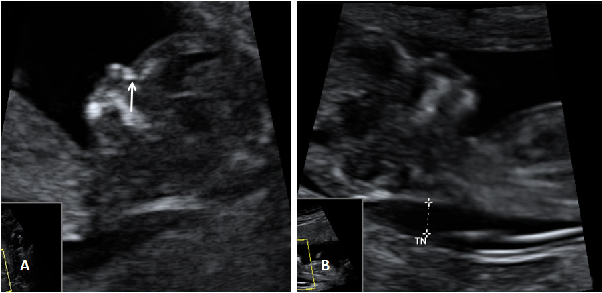

Ecografía Embarazo 2D y 3D Semana 12 - PRUEBAS DIAGNÓSTICAS